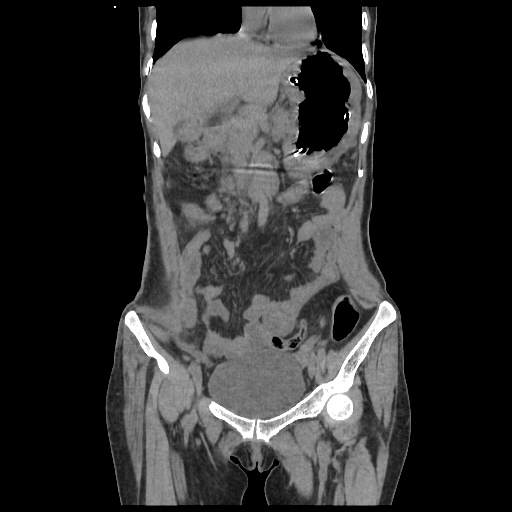

Radiological images:

CT-Scan investigation done on 16Apr16